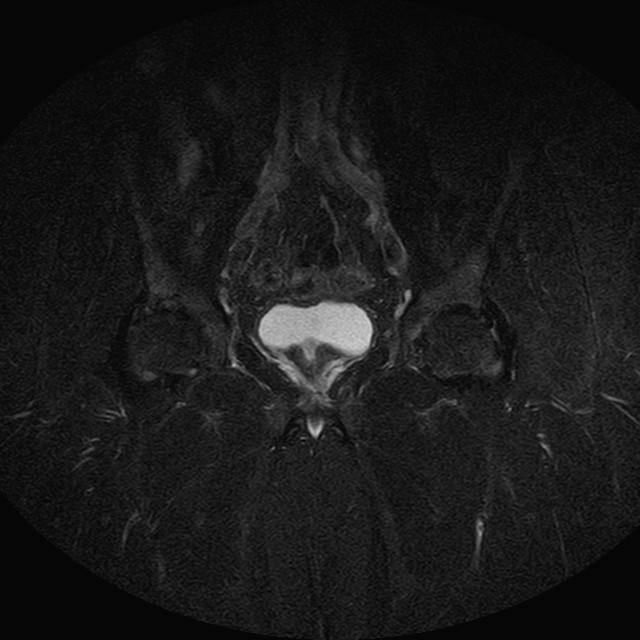

eSTIR

Evidenti e simmetriche alterazioni osteofitosiche in regione coxo femorale con riduzione delle rime articolari. Degenerazione completa del cercine glenoideo. Non attuali segni di versamento articolare. Non segni di edema osseo che escludono attuale algodistrofia od osteonecrosi. Lieve e simmetrica riduzione del trofismo della muscolatura glutea.